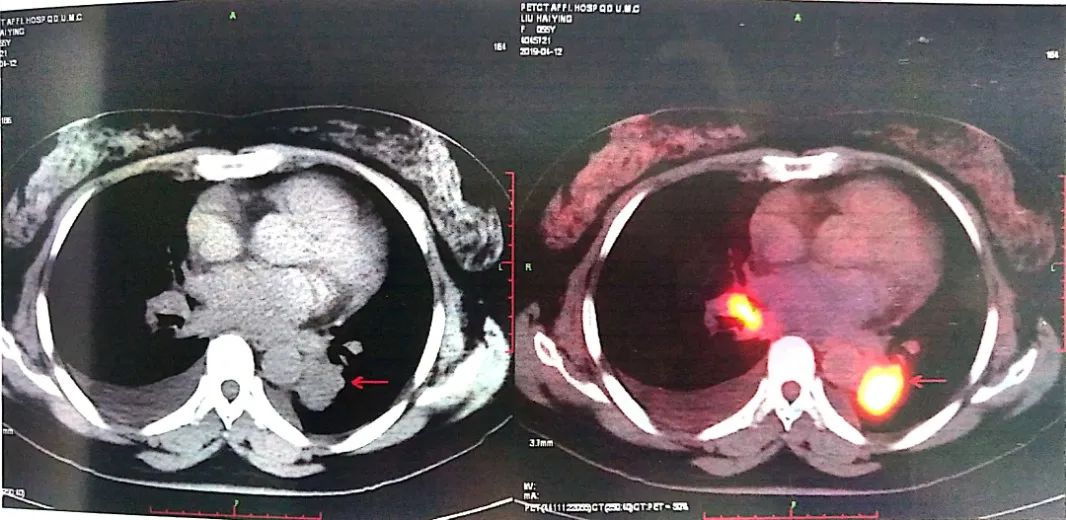

2019-04-12 PET-CT显示①右肺下叶后基底段胸膜下软组织密度肿块(大小26*30mm)。

②左肺下叶纵隔旁软组织密度肿块(大小28*31mm)。

③双肺门、纵隔内隆突下、气管旁、主肺动脉窗、血管前间隙、右侧颈部Ⅴ区及锁骨区多发增大淋巴结。

至此为止,患者的诊断为:肺恶性肿瘤 小细胞癌 广泛期 cT4N3M0 IIIC期(病灶1:右肺下叶,病灶2:左肺下叶),此时先给予标准化疗方案,EP方案:依托泊苷100mg/㎡  d1-3+顺铂75mg/㎡ d1-2 q21d*2。结果如下: